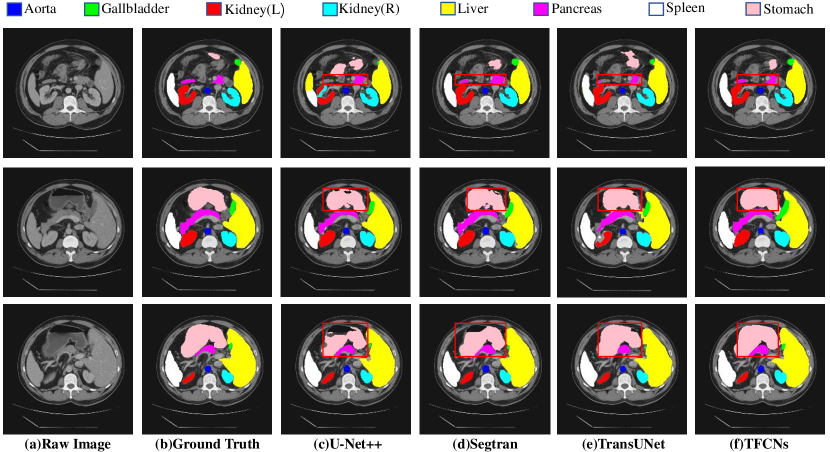

As shown in Table 2, these methods including Transformers, i.e. TransUNet [2], Segtran [24], and our TFCNs achieves better performance when compare with other methods. Especially, our method has a slight lead in terms of Dice coefficient and Jaccard coefficient when compared to TransUNet [2] and Segtran [24]. We believe this improvement is brought by the Dense Block we add, which is able to enhance the transmission of semantic information in the main pipeline.

From Table 2, it can be observed that our method achieves more accurate results than other approaches on some organs that are difficult to be segment, such as the Gallbladder and Pancreas. Since these tiny organs occupy a relatively small proportion in the original image, other approaches are easy to wrap other interfering information when extracting features from the areas containing these tiny organs. Conversely, through the utilization of the designed CLAB module, our model is able to pay more attention to these tiny organs themselves instead of those irrelevant areas. Meanwhile, for other organs, the results achieved by our method are also in the top 5.